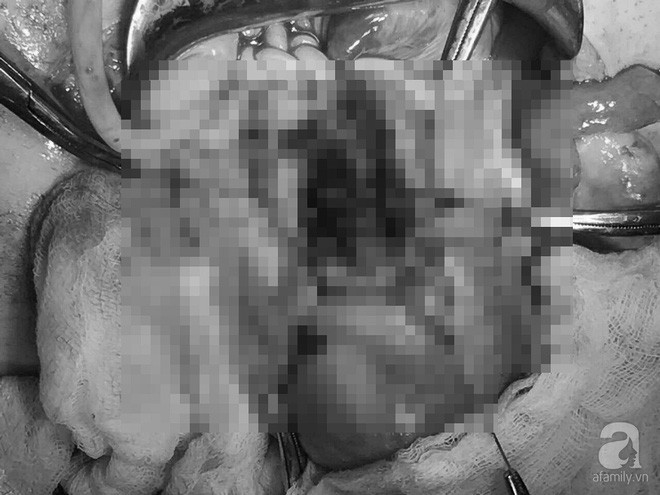

Các bác sĩ (BS) nhận định đây một trường thai bám ở sẹo mổ lấy thai có biến chứng. Bệnh nhân có vết mổ cũ lấy thai hai lần, hình ảnh trên siêu âm thấy khối nhau thai to, xâm lấn hết cơ tử cung vùng vết mổ, có nhiều mạch máu tăng sinh, tiên lượng có thể có tổn thương bàng quang. Tiến hành hội chẩn liên viện khẩn cấp, BS quyết định phẫu thuật để bóc khối thai bám sẹo mổ cũ.

Khối nhau thai xâm lấn hết cơ tử cung vùng vết mổ, tiên lượng có thể có tổn thương bàng quang.

Cuộc phẫu thuật diễn ra với sự phối hợp của ekip các BS Sản phụ khoa, Niệu khoa, Gây mê hồi sức, Huyết học truyền máu… Sau 1 giờ 20 phút phẫu thuật, khối thai với đường kính 6cm được bóc trọn khỏi sẹo mổ cũ, khâu phục hồi sẹo mổ và bảo tồn được tử cung cho bệnh nhân. Quá trình phẫu thuật, bệnh nhân đã được truyền 2 khối hồng cầu trước mổ để ổn định tình trạng thiếu máu. Hiện chị Tr. đã không còn đau bụng, hết chảy máu và đang hồi phục tốt.